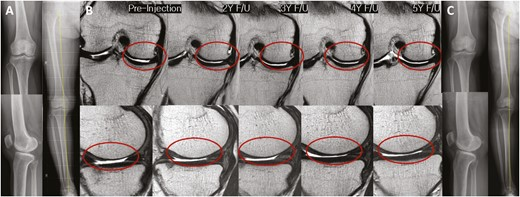

2022年5月14日,韓國江東慶熙大學(xué)醫(yī)院骨科在行業(yè)期刊《干細(xì)胞轉(zhuǎn)化醫(yī)學(xué)》上發(fā)表了一篇關(guān)于《關(guān)節(jié)內(nèi)注射間充質(zhì)干細(xì)胞治療膝骨關(guān)節(jié)炎的安全性和有效性:5年隨訪研究》的研究成果。【4】

招募了11名膝關(guān)節(jié)骨關(guān)節(jié)炎患者,并在單次關(guān)節(jié)內(nèi)注射自體高劑量 (1.0×108?) ADMSCs 的5年隨訪期間進行了系列評估。

- 系列MRI檢查顯示,注射后3年內(nèi)MFC軟骨缺損面積呈減少趨勢,治療后5年內(nèi)未見明顯惡化(圖 4)。

- 內(nèi)側(cè)間室軟骨WORMS評分在注射后2至3年間均有明顯改善(2年,P=0.029;3年,P=0.031)(表3)。

- 治療后3年內(nèi),總體WORMS顯示出顯著改善,從73.4±27.8顯著下降至70.5±26.8(6個月;P= 0.020)、65.5±29.4(2年,P=0.016)和66.5±30.7(3年,P=0.041)(表3)。

- WORMS子評分還顯示,在注射后2至3年內(nèi)、注射后2年內(nèi)和注射后3年內(nèi),總軟骨狀態(tài)、骨髓水腫和滑膜炎均有顯著改善。

綜上所述,VAS和總WOMAC評分在注射后6個月以及直到最新隨訪時均顯著改善。總WORMS在注射后3年內(nèi)顯著改善。

單次關(guān)節(jié)內(nèi)注射自體高劑量ADMSCs可在5年內(nèi)提供安全的臨床改善,且不會出現(xiàn)放射學(xué)加重。此外,骨關(guān)節(jié)炎膝關(guān)節(jié)的結(jié)構(gòu)變化在長達(dá)3年的時間內(nèi)顯示出顯著改善,這表明它可能是膝關(guān)節(jié)OA患者的疾病改良治療的一種可能選擇。